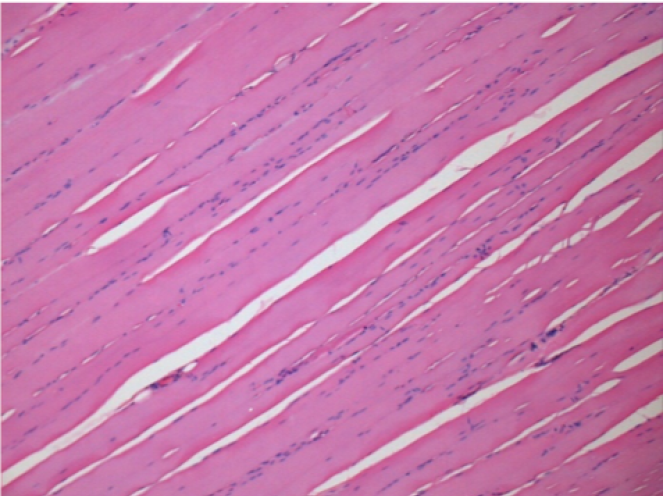

1 mes después de la inyección de Endopeel 0,1 ml en el músculo pretibial derecho.

¡Lo que se ve en negro en las imágenes no es una necrosis como podrían imaginar algunos científicos!

De hecho, hay que tener en cuenta 4 conclusiones

08